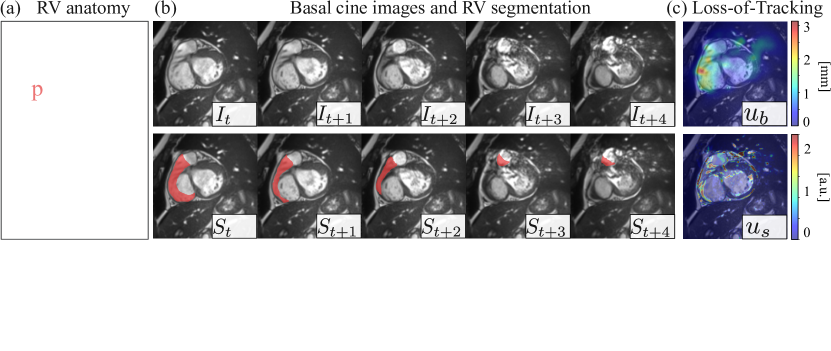

Refer to caption

Figure 1: (a) Anatomy of LV and RV. The basal imaging plane covers the right ventricle outflow tract (RVOT), pulmonary valve (P), and tricuspid valve (T) [20]. (b) A short-axis basal slice contains atria (in green), P (in blue), and RVOT (in red), with complex and varying layouts. (c) Motion tracking has high uncertainty here (ubsubscript𝑢𝑏u_{b} and ussubscript𝑢𝑠u_{s}, defined in Section 2.1), indicating loss-of-tracking. (d) RV segmentation by 10 Bayesian ensembles exhibits high uncertainty, resulting in a poorly reproducible volume estimation ranging from 0.2 to 37.8 mL.

Segmentation of basal slices is intrinsically challenging, because clinical cine MRI is 2D+t𝑡t, with each plane imaged in a separate breath-hold, unable to capture the complex 3D+t𝑡t spatiotemporal motion at the base. Ventricles, atria, and valves all have inter-planar movements [16, 26], as shown in Fig. 1 (b). This complicates basal segmentation, resulting in quantitative errors of RV assessment [4, 16].

More specifically, RV segmentation error stems from the region of the right ventricle outflow tract (RVOT). RVOT is a pathway where the blood exits RV and enters the pulmonary artery [11], spanning from the right side of the tricuspid valve to the pulmonary valve [8] (Fig. 1 a). RVOT needs to be included for accurate RV quantification, but it is often overlooked in the annotations of public CMR datasets [26, 4, 5, 16]. Common protocols delineate RV when the full cavity is covered [4, 5, 16] while RVOT is labeled as RV or background depending on cases or observers. This inconsistency in the annotation can affect the confidence of the neural network [13]. Segmentation models, even when trained on the same dataset [9, 15, 13], will have high uncertainty on basal slices, resulting in low reproducibility of volume quantification. A typical example is shown in Fig. 1 (d), where different segmentation models make varying RV predictions, indicating low reproducibility of RV volume estimation [9, 29, 28]. This undermines the reliability of the assessment of RV function.

However, the same principle does not apply to the RV base, because of the strong in-plane anatomy change (Fig. 1 b). Intuitively, estimating the motion between temporal frames at RV base is ill-posed, i.e. a well-trained motion tracking model will fail to track due to the inter-planar motion, a phenomenon we hereafter call loss-of-tracking. Hence, instead of leveraging the temporal coherence, we propose the opposite: we make use of the temporal incoherence, which can be identified by motion tracking uncertainty. This uncertainty highlights the inter-planar motion of different structures (Fig. 1 c) and is highly informative.